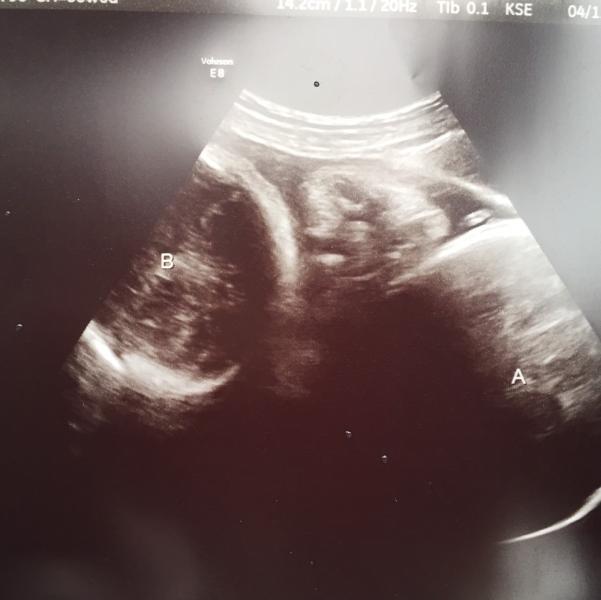

My girls are both head down and resting on my left hip. From about 20 weeks on, I didn't even think about a vaginal birth. One was always breech. To think I could deliver the way I originally planned (natural vaginal), makes me giddy with excitement. But there's still a lot to consider. If baby A kicks B on the way out to where she flips, then I'd be knocked out bc there wouldn't be time for an epidural to work. Then I'd be recovering from both vaginal and c section, but more importantly I'd miss the birth of my other babe. Oh and this will happen in a week, so I better decide soon. Thoughts?